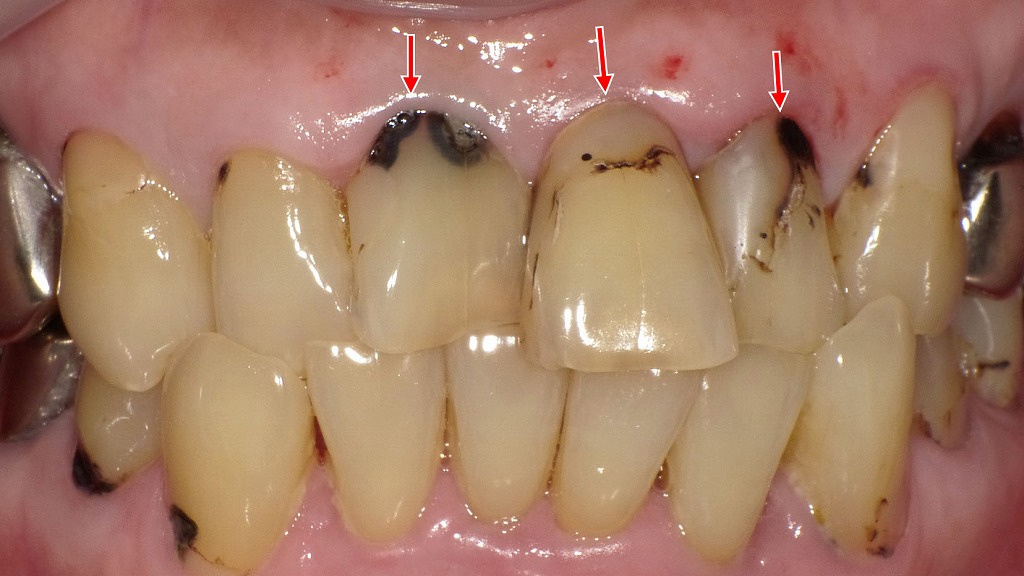

経年劣化・着色・境界部分が変色した症例

コンポジットレジンは見た目が自然で使いやすい材料ですが、経年変化によって 着色・変色・表面の摩耗・欠け(チッピング) が起こりやすい傾向があります。写真では、修復部の微小な欠け、段差の形成、境界部分の変色が認められ、レジン特有の劣化が進行した状態が確認できます。また、噛む力が強くかかる部位では破折や脱離が起こることもあり、定期的なメンテナンスや再修復が必要になる場合があります。